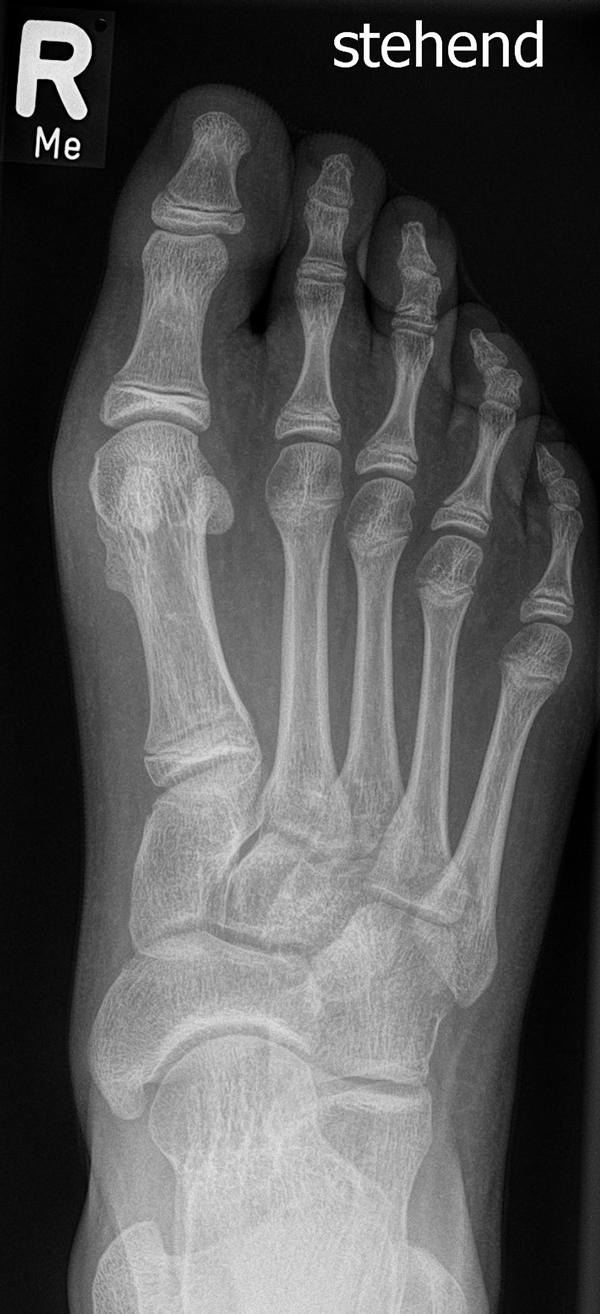

In der Regel bestehen aktive Wachstumsfugen bei Mädchen bis zum 12. und bei Jungen bis zum 14. Lebensjahr, mit Abweichungen von einem Jahr nach unten und nach oben. Präzise Informationen unter anderem darüber gibt das präoperative Röntgenbild (Abb. 2).

Abb. 2 a-c: offene Wachstumsfugen MT I Basis und Zehen (a), teilweise geöffnete Wachstumsfugen (b) und geschlossene Wachstumsfugen (c).

Damit die minimalinvasive Fußchirurgie zur Korrektur kindlicher oder jugendlicher Fußdeformitäten erfolgreich angewendet werden kann, erfordert die präoperative Diagnostik Röntgenbilder in drei Ebenen am stehenden Fuß. Röntgenbilder ohne Belastung des Fußes sind nicht zielführend. Im Fall von schweren Rückfußdeformitäten wird das obere Sprunggelenk in die radiologische Diagnostik mit einbezogen in Kombination mit der Rückfußaufnahme unter Belastung („Saltzman View“). Das OSG wird in zwei Ebenen geröntgt. Die streng seitliche Aufnahme des OSG kann bei den komplexen Fußdeformitäten mit der seitlichen Aufnahme des Fußes unter Belastung kombiniert werden. Das reduziert die diagnostische Strahlenbelastung der Kinder.